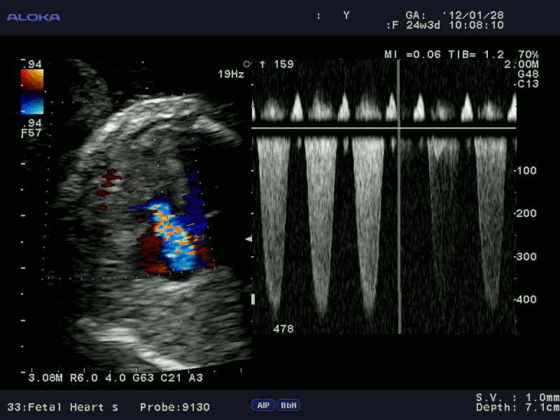

Допплерэхокардиография позволяет измерить все вышеперечисленные параметры, которые очень важны при оценке детской сердечной патологии (врожденные пороки) без использования инвазивной процедуры — катетеризации сердца. Помимо этого, назначение эхокардиографии с допплеровским анализом ребенку не несет никакой угрозы по сравнению с компьютерной томографией, где используется рентгеновское излучение.

3. Допплер-эхокардиография - импульсный, непрерывно-волновой, цветовой, цветовой М-режим, энергетический, тканевой цветовой, тканевой импульсный, тканевой С-режим и т. д. - метод, позволяющий неинвазивно оценить параметры центральной гемодинамики. Активное применение методики в медицине можно отнести к началу 80-х годов.

Цветовой допплер (Color Doppler). Цветовой допплер - аналог импульсного допплера, где направление и скорость кровотока картируется различным цветом. Так кровоток к датчику принято картировать красным цветом, от датчика - синим цветом. Турбулентный кровоток картируется сине-зелено-желтым цветом.